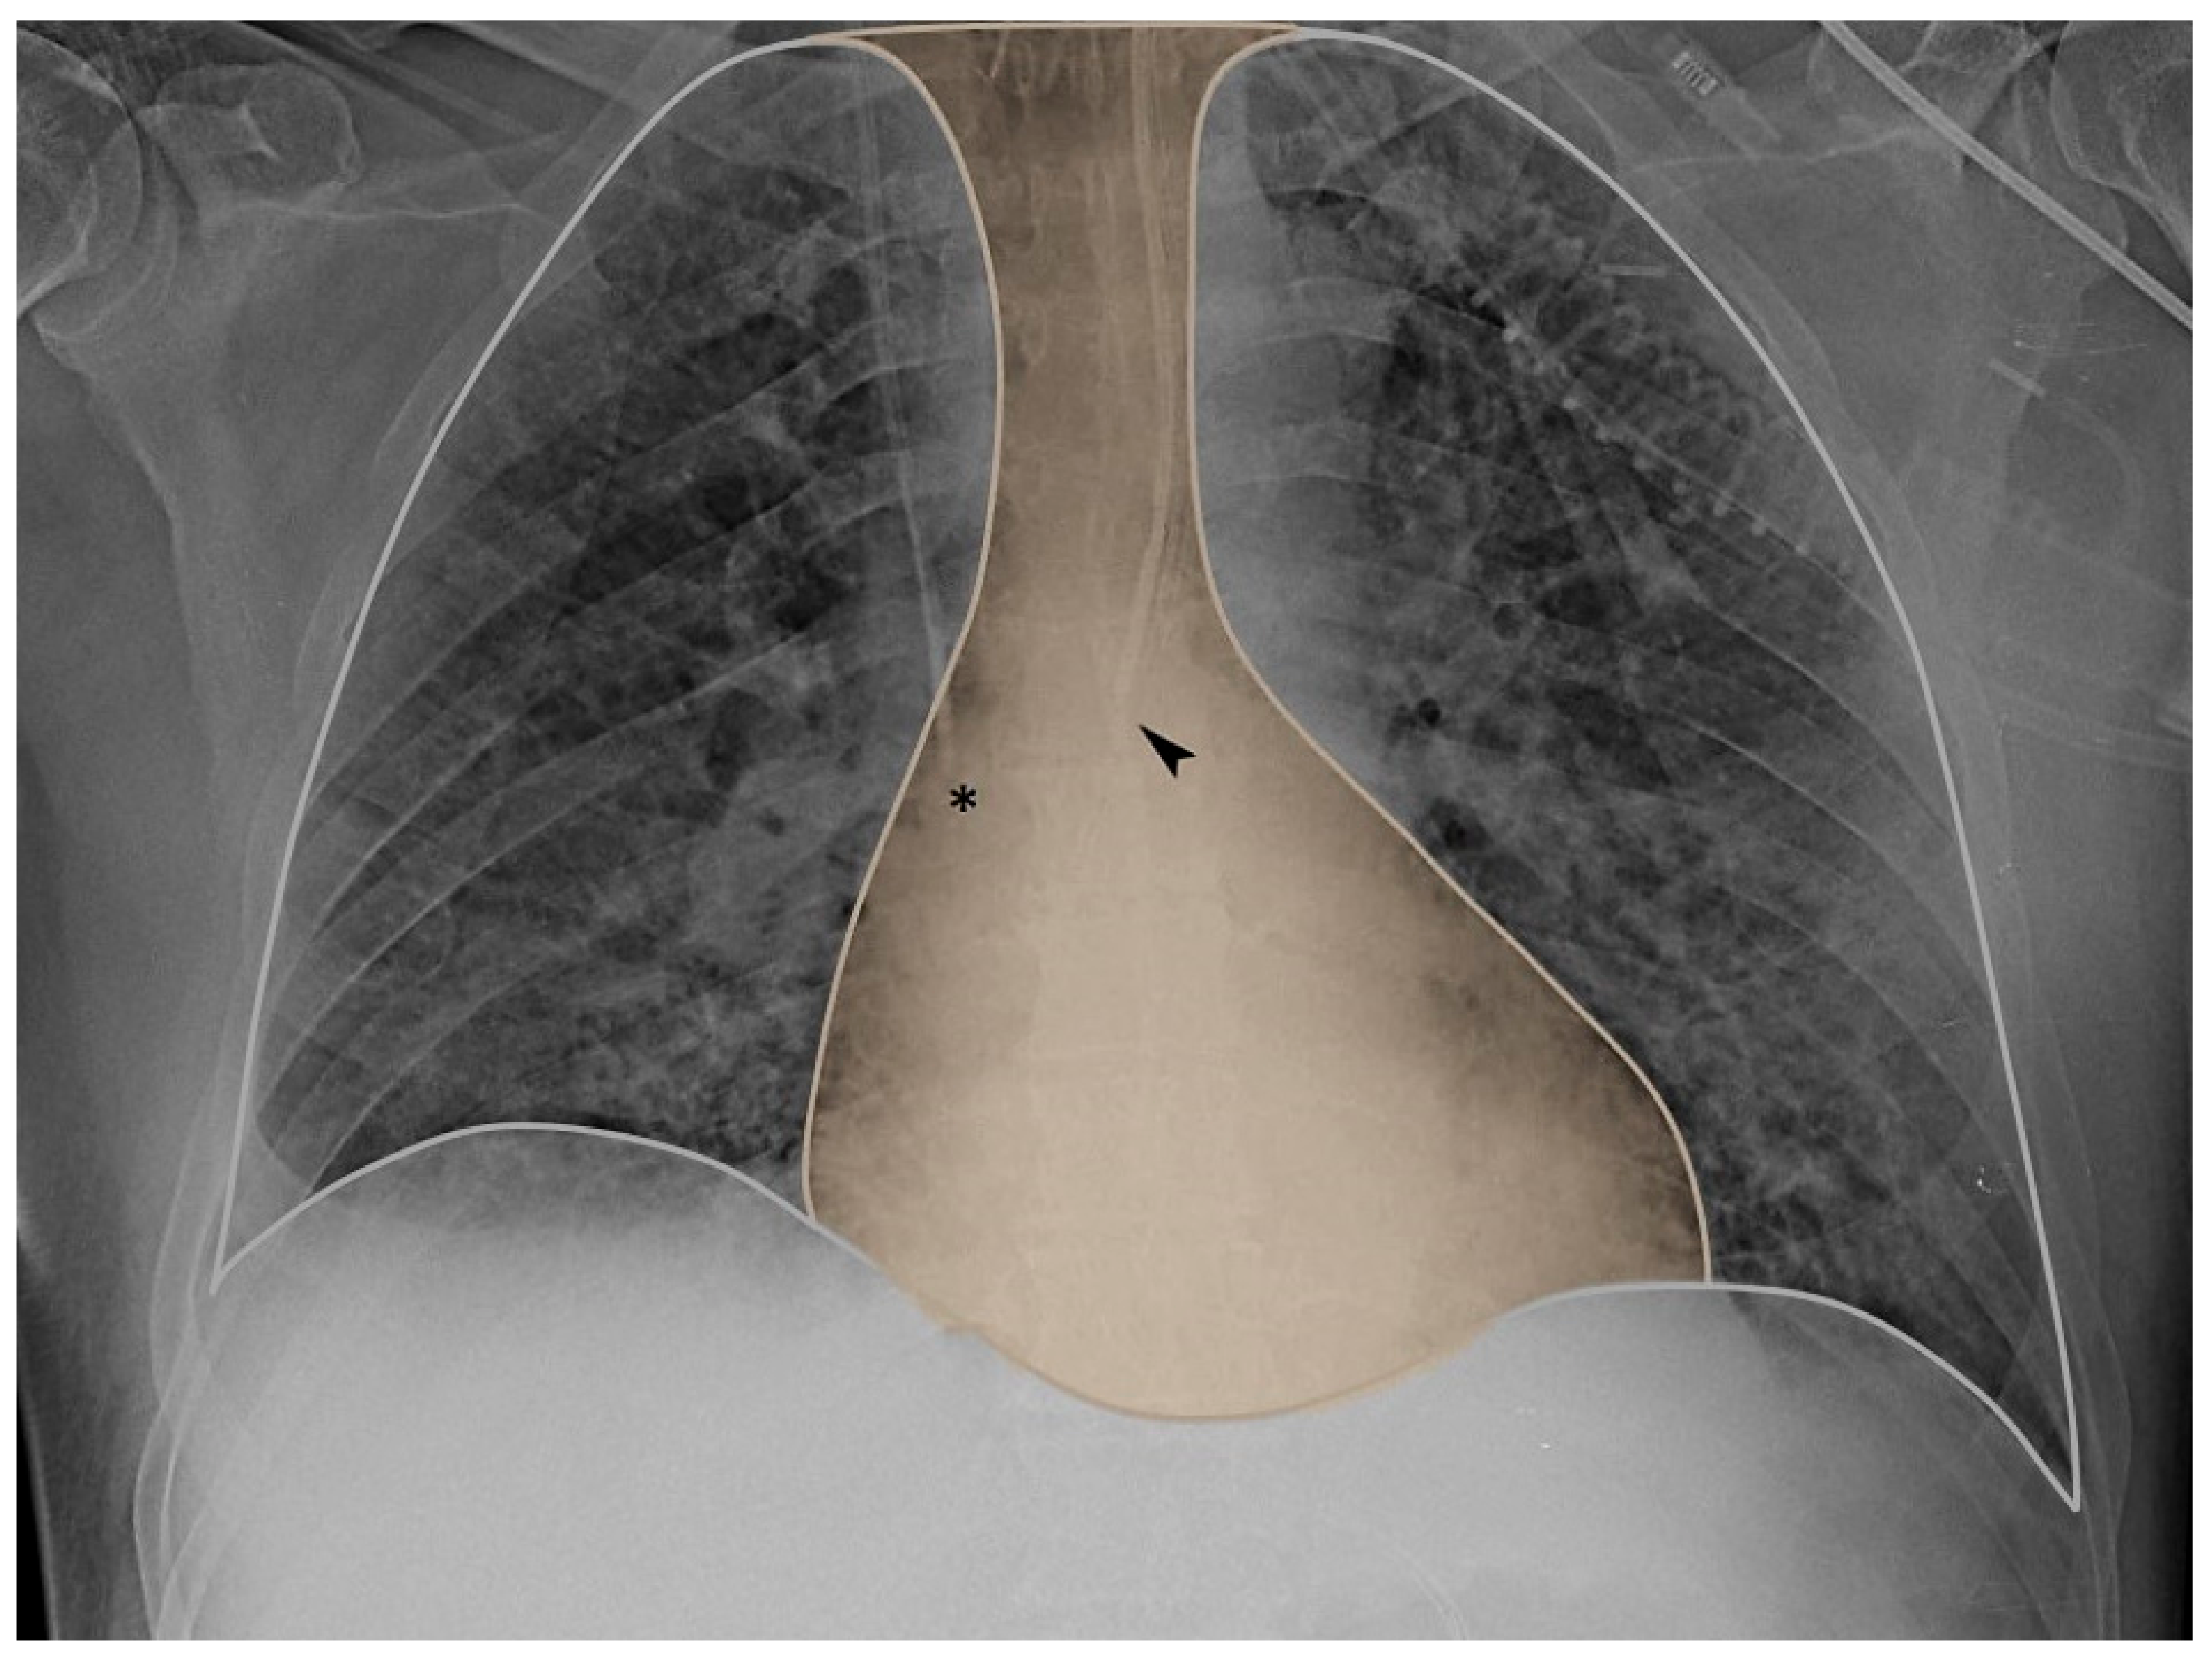

- La Colla, L.; Bronshteyn, Y.S.; Mark, J.B. Respiratory Variation in Central Venous Pressure (CVP) to Guide Ventilatory Support in Coronavirus Disease 2019 (COVID-19)–Related Lung Injury. J. Cardiothorac. Vasc. Anesth. 2021, 35, 345–347. [Google Scholar] [CrossRef]